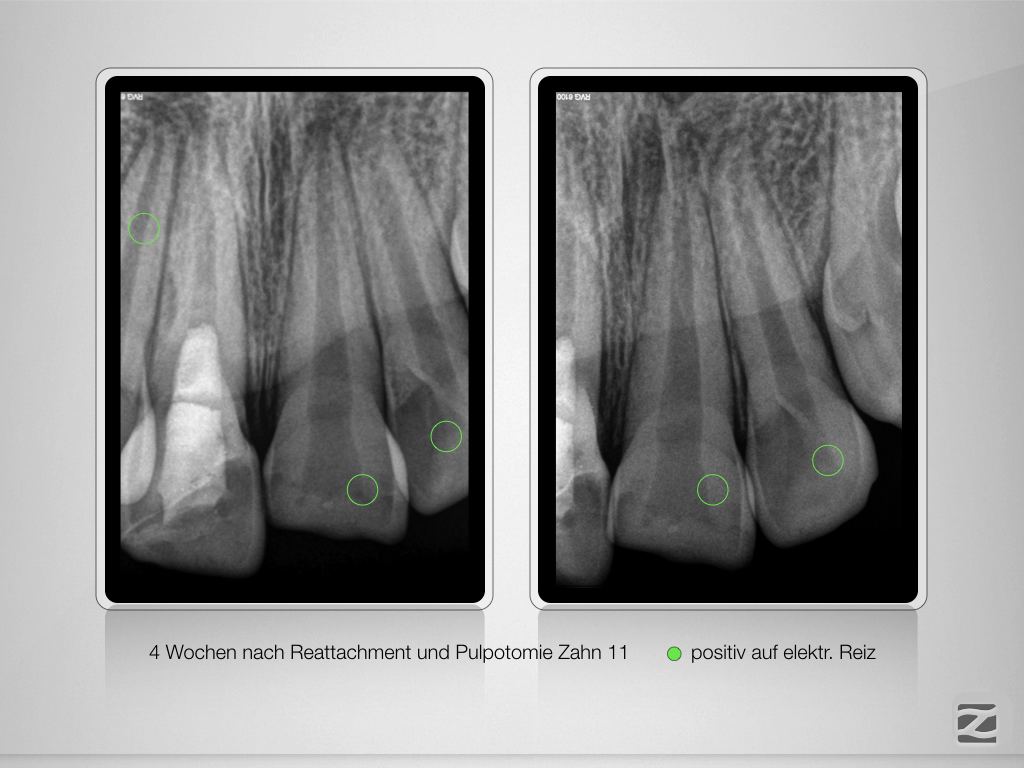

And the show goes on-Trauma, die Zweite.